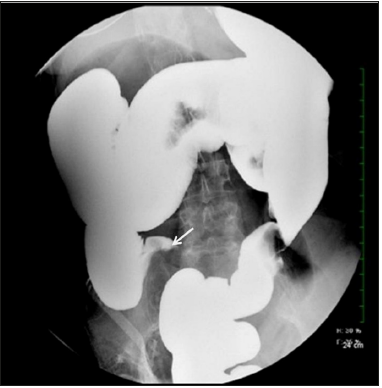

The patient was initially treated with intravenous fluids, nasogastric tube with suction, and nothing by mouth. Surgical consultation was obtained and given the patient’s clinical stability and stool burden on imaging with no obvious transition point, the surgeon believed the presentation to favor fecal impaction over cecal volvulus. Continued conservative management with enema was recommended. Patient had a large bowel movement after receiving the enema, however her distention and abdominal pain did not improve. Barium enema was then performed and confirmed cecal volvulus (Figure 2).

Figure 2:Barium enema film. Despite repositioning patient multiple times and waiting, no contrast was passing. “Bird’s peak” appearance is compatible with cecal volvulus (arrow).

In our case, the appendix was not well visualized on the CT scan. It was also difficult to differentiate the dilation of the cecum was due to volvulus or fecal impaction given a large amount of fecal burden and no obvious transition point. In view of this, a barium enema was the appropriate next step. It was both therapeutic for the fecal impaction, and also identified the cecal volvulus which is an emergent condition due to potential for intestinal ischemia and infarction. The classic “bird’s beak” appearance under the barium enema is suggestive of colonic volvulus. The management of cecal volvulus is either endoscopic decompression or surgical intervention. The success rate of endoscopic decompression of cecal volvulus is only 10-15% and given that cecal volvulus also has high ischemic rate, surgical intervention is often preferred [8]. In our case, considering the low endoscopic successful rate, especially with fecal impaction, an urgent exploratory laparostomy was performed by general surgery.